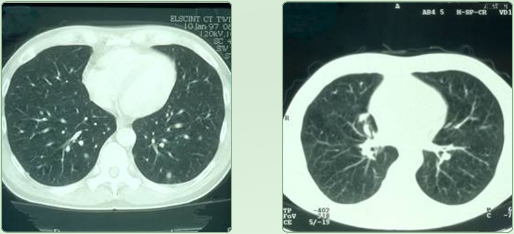

Lungenmetastasen vor RTH - Lungenmetastasen nach RTH

Bronchial - CA

diffuse Lungenmetastasierung eines mucinösen Adeno - CA - s unklaren Ursprungs (CUP-Syndrom) ED 1/97 2 malige Regionale Chemotherapie in Kombination mit 12 Behandlungen regionaler Tiefenhyperthermie (3 x / Woche) führten zur Vollremission; aus |

Mastall H. Zeit- und situatiosgerechte Einsatzmodelle für komplementäre Verfahren während |

konventionell-onkologischer Therapien. |

32. Medizinische Woche Baden-Baden 1998; 02.XI |